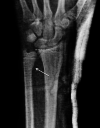

Isolated distal ulna epiphyseal plate injuries are very rare and are often associated with early epiphyseal plate arrest. A 13-year-old boy sustained an isolated minimally displaced Salter-Harris type II fracture of the left distal ulna following a fall from a bicycle. The fracture was reduced, and a long arm plaster cast was applied for four weeks. At the six-month follow-up, the patient presented with a painless, full range of movement of the left wrist, but on radiological examination, a mild shortening of the ulna was detected. We plan to regularly evaluate this patient until distal epiphyseal plate closure and surgically intervene if necessary. To our knowledge, this is the third Salter-Harris type II distal ulnar fracture ever reported, and the second treated nonoperatively. It was shown to be associated with a mild growth disturbance. Although Salter-Harris type II injuries are considered benign, surgeons should closely evaluate this rare type II isolated distal ulnar fracture and inform parents regarding possible future complications, which range from clinically insignificant cosmetic deformity to severe instability of the distal radioulnar joint, depending on the degree of shortening.